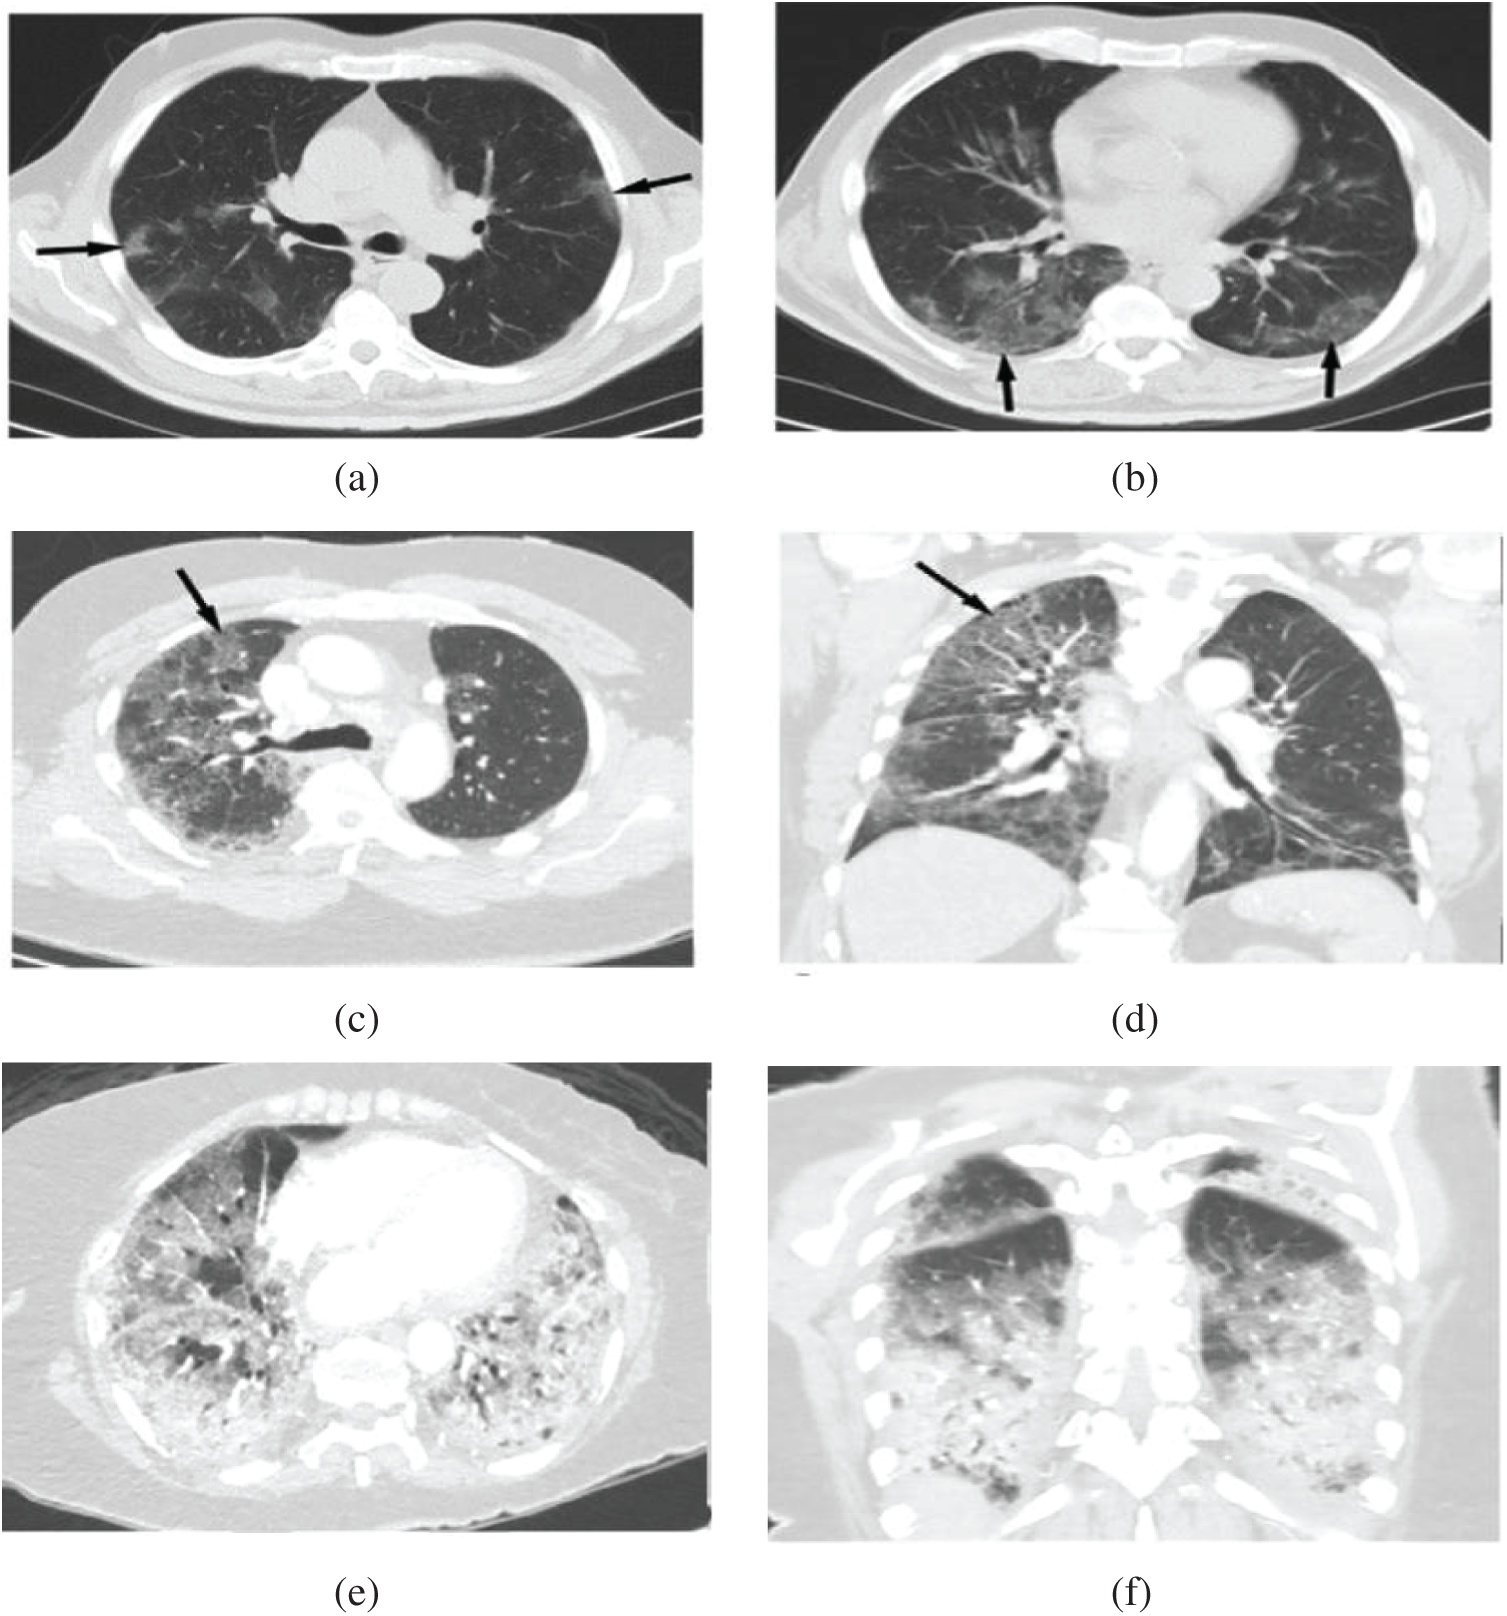

As reported in [2,3], the trademark of COVID-19 is the two-sided distribution of patchy shadows and conspicuous ground-glass opacity (GGO) lesions in peripheral and posterior lungs, with the GGO being the most common finding. In the GGO, certain parts of the lung appear like a hazy shade of gray, as seen in Figs. 1a and 1b instead of black with fine white lung outlines for blood vessels. It appears like a frosted window in winters that suggest a partial filling of air spaces or alveoli in the lungs by fluids. In severe or more advanced infections, more fluid buildup in the lungs and the appearance of GGO becomes “Solid White Consolidation” (SWC), as shown in Figs. 1e and 1f. In the same context, there is a finding called “Crazy Paving Pattern” (CPP), as reflected in Figs. 1c and 1d, which occurs because of the swelling of interstitial space on lung lobules’ walls while making walls look denser like white lines contrary to hazy GGO background. The design is identical to an odd-shaped stone used to pave the driveway.

Figure 1: Shows chest CT scan: (a, b) Hazy opacities in both lungs (arrows), (c, d) The crazy paving pattern (arrow), (e, f) Widespread solid consolidations [5]